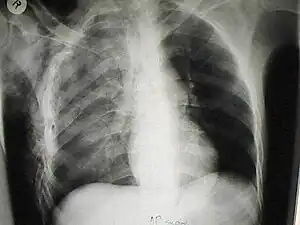

X-ray

Chest X-ray is the most common method used for diagnosis,[37] and may be used to confirm a diagnosis already made using clinical signs.[20] Consolidated areas appear white on an X-ray film.[42] Contusion is not typically restricted by the anatomical boundaries of the lobes or segments of the lung.[27][43][44] The X-ray appearance of pulmonary contusion is similar to that of aspiration,[32] and the presence of hemothorax or pneumothorax may obscure the contusion on a radiograph.[25] Signs of contusion that progress after 48 hours post-injury are likely to be actually due to aspiration, pneumonia, or ARDS.[10]

Although chest radiography is an important part of the diagnosis, it is often not sensitive enough to detect the condition early after the injury.[35] In a third of cases, pulmonary contusion is not visible on the first chest radiograph performed.[7] It takes an average of six hours for the characteristic white regions to show up on a chest X-ray, and the contusion may not become apparent for 48 hours.[7][27][43] When a pulmonary contusion is apparent in an X-ray, it suggests that the trauma to the chest was severe and that a CT scan might reveal other injuries that were missed with X-ray.[2]